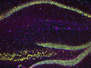

Venomous Painkiller

This eight-inch-long Chinese redheaded centipede may not be the most obvious remedy for chronic pain, but a molecule derived from its venom is proving to be a powerful painkiller. The molecule, known as Ssm6a, is a peptide – a smaller version of a protein – that has been fine-tuned by millions of years of evolution to block a cellular gateway called sodium channel NaV1.7. This channel is involved in pain sensing, and blocking it inhibits the ability of nerve cells to send pain signals to the brain. When Ssm6a was tested on mice, it relieved pain more effectively than morphine and without any side effects. The researchers who discovered the peptide will now try to tweak its molecular structure to optimise its impact and make it safe for humans. If they’re successful, Ssm6a could join the dozens of venom-derived peptides already in the drug development pipeline.